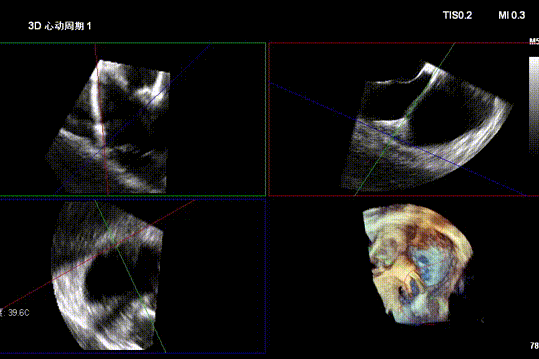

After general anesthesia, the patient underwent jugular vein puncture to establish access. An 18Fr delivery sheath was advanced over a super-stiff guidewire to the mid-to-lower right atrium. Under ultrasound guidance, the delivery system was introduced. A 14T K-Clip® and a 16T K-Clip® device were implanted at the postero-septal commissure annulus and the antero-posterior commissure annulus, respectively. The angle between the device and the annular plane was adjusted through controlled flexion and rotation to orient the device tip toward the target site. Using ultrasound MPR mode, the anchor component was advanced into the annulus. After traction confirmed stability, the clip arms were opened and apposed to the annulus. The anchor component was then retracted to close the clip arms, achieving annuloplasty. The effect was evaluated as satisfactory, and the clip components were deployed.

Advancing anchor component under MPR view

Opening clip arms, adjusting orientation, and apposing to the annulus

Closing the clip and evaluating effect under ultrasound

Second clip placed at postero-septal commissure using the same steps

Both clips stable

Postoperative

2. Annuloplasty Effect: